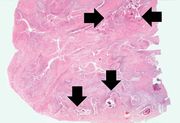

| 04:03, 21 August 2013 | IPLab10Candidiasis7.jpg (file) | 77 KB | This is a low-power photomicrograph of the kidney from this same case. Note the Candida colonies (arrows). The pseudohyphae are evident around the periphery of these colonies even at this low magnification. | 1 | |